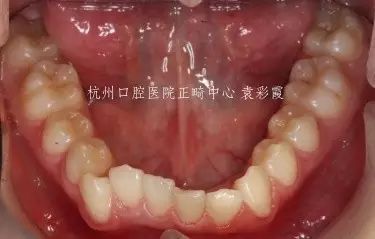

儿子

父亲